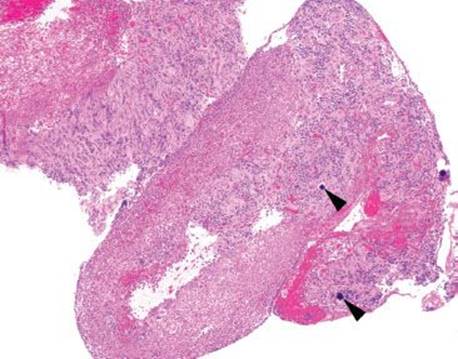

90Yttrium-labeled microspheres are used in the targeted treatment of unresectable primary and metastatic hepatic malignancies, a process termed “selective internal radiation therapy.” The microspheres are delivered via catheter into the hepatic artery to preferentially target the neoplastic cells since the neoplastic cells derive most of their blood supply from the hepatic artery and the nonneoplastic hepatocytes derive the majority of their blood supply from the portal vein. This targeted nature of delivery allows for a higher dosage of radiation than that which would be tolerable under systemic radiation therapy, and theoretically minimizes the toxic effects of the radiation to uninvolved organs; however, when the 90yttrium-labeled microspheres inadvertently enter the arteries supplying the stomach, duodenum, or pancreas, they can cause unintended radiation damage to nontargeted organs at relatively high doses of radiation. Recall, radiation injury consists of lamina propria hyalinization, atypical stromal, endothelial, and epithelial cells, and prominence of ectatic, damaged vessels. See also Radiation Gastritis Pattern, Vascular and or Hemorrhagic Pattern in this chapter (Figs. 2.224–2.227). 90Yttrium-labeled microsphere-related esophagitis, gastritis, duodenitis, pancreatitis, and cholecystitis have been reported.181,182,193,194 The microspheres are 30 to 40 μm in diameter with a maximum penetration of 11 mm, a half-life of 2.5 days, and emissions can occur as far out as 14 days postdelivery (Figs. 2.251–2.254).193,194

Figure 2.251 90Yttrium-labeled microsphere gastritis. At scanning magnification, this biopsy features foveolar hyperplasia, patchy chronic inflammation, and scattered 90yttrium-labeled microspheres deep in the mucosa (arrowheads). The microspheres are perfectly round, uniformly opaque, and deep dark purple.

Figure 2.252 90Yttrium-labeled microsphere gastritis. On higher power, these microspheres can look like little else, they are so characteristic. Of course, they have raised concerns for Schistosomiasis, psammoma bodies in association with neuroendocrine tumors, dystrophic calcifications, and embolization material. In this example, the microspheres (arrowheads) are surrounded by a pool of brisk chronic inflammation.

PEARLS & PITFALLS

90Yttrium-labeled microspheres are usually seen in association with an alarming endoscopic appearance (Fig. 2.224), radiation injury pattern, and horrendous epithelial change. These changes can be so concerning that dysplasia or carcinoma are often diagnostic considerations. In these cases, recognition of the background radiation injury pattern and the characteristic microspheres are essential to arriving at the correct diagnosis. In addition, a CMV immunostain is worthwhile in all cases, as the diagnostic CMV-infected cells can be easily obscured by the radiation injury.

Anecdotally, 90yttrium-labeled microspheres can be confused for Schistosomiasis, psammoma bodies in association with neuroendocrine tumors, dystrophic calcifications, and embolization material. In these types of cases, careful attention to the background radiation injury pattern serves as important red flags for the correct diagnosis.